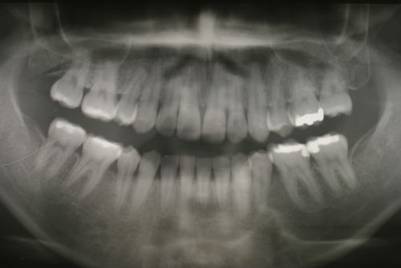

連続抜去法(10歳ごろ犬歯の萌出寸前に第一小臼歯を抜歯する方法です)

左上側切歯の被害はワイヤーを短期間使用しています

5年後 きれいな歯列になっています。 時期によれば小臼歯4本抜歯でここまできれいに並びます